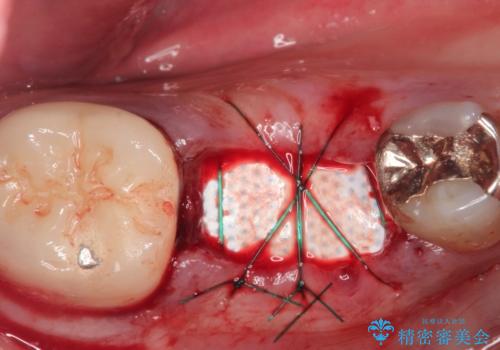

破折の深さが歯根まで及んでいたため抜歯を行いました。

抜歯をしたあと骨が痩せないよう抜歯直後に骨補填材を入れています。